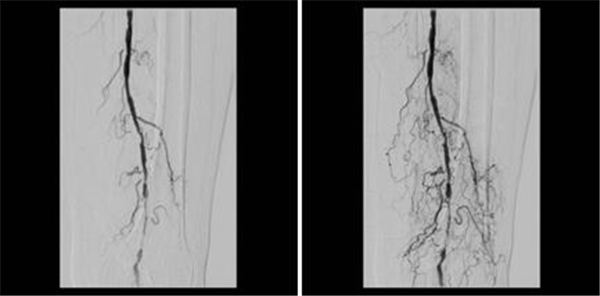

介入治疗按计划如期进行,动脉造影果然如CTA所示:双侧股动脉都有狭窄,尤其以左侧明显,多处狭窄从股动脉延续到腘动脉,周边可见侧枝循环形成,如图~